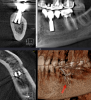

OMFS Опубликовано 19 июля, 2013 Поделиться Опубликовано 19 июля, 2013 История:имплантация в 2006 несколько дней назад поломался мост, появилась подвижность и после небольшая болезненность при накусывании.КТ 2012 г.прицельный снимок вчерашний.Достали сегодня. 4 Ссылка на комментарий

kriokov Опубликовано 19 июля, 2013 Поделиться Опубликовано 19 июля, 2013 (изменено) Это Новокузнецк или что-то другое?похож на болт новокузнецкий. Лет 10 назад приезжала к нам Копысова с агитационным паровозом, такой же в супнаборе у нее был Изменено 19 июля, 2013 пользователем kriokov Ссылка на комментарий

kriokov Опубликовано 19 июля, 2013 Поделиться Опубликовано 19 июля, 2013 (изменено) Не помнишь поверхность была шершавая или гладкая?поверхность точно шершавая, позиционировалось как штука изготовленная из пористого никелид - титана с эффектом памяти формы и помоему изготовленная методом порошковой металлургии. Меня отправили туда скобки смотреть омего образные с памятью формы, для остеосинтеза нижней челюсти . Я послушал , шефу доложил. И решили мини и микропластины купить немецкие, из Бертизгадена.Еще какую то скобку показывали для шинирования подвижных зубов. Но это для меня уже не очень понятно было, поэтому ушел. Изменено 19 июля, 2013 пользователем kriokov 1 Ссылка на комментарий